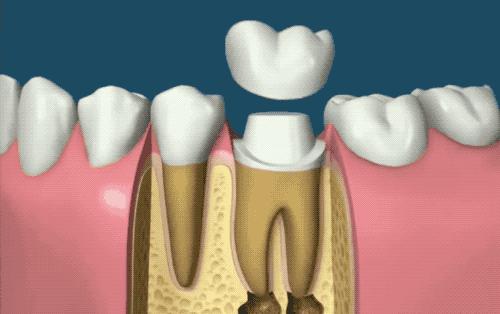

现代拔牙技术强调无痛、微创、快速恢复,这家小店引进了国际先进的牙科设备,如数字化口腔扫描仪和三维口腔打印机等,为患者提供更加精准、个性化的诊疗方案,医生运用先进的麻醉技术,确保患者在无痛状态下接受手术,微创技术的应用大大减少了手术过程中的创伤,缩短了恢复时间。

这家小店的拔牙技术是现代与传统完美结合的典范,他们不仅保留了传统拔牙技术的精髓,而且融入了现代科技的创新成果,你可以体验到传统拔牙技术的精湛技艺,更能感受到现代拔牙技术的神奇魅力。